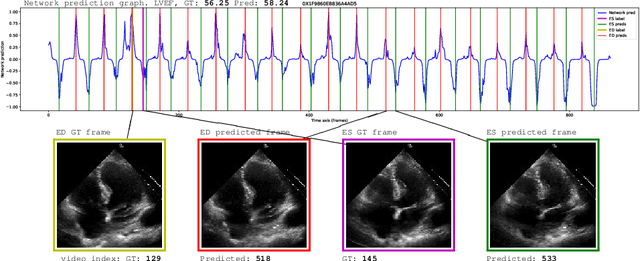

Cardiac ultrasound imaging is used to diagnose various heart diseases. Common analysis pipelines involve manual processing of the video frames by expert clinicians. This suffers from intra- and inter-observer variability. We propose a novel approach to ultrasound video analysis using a transformer architecture based on a Residual Auto-Encoder Network and a BERT model adapted for token classification. This enables videos of any length to be processed. We apply our model to the task of End-Systolic (ES) and End-Diastolic (ED) frame detection and the automated computation of the left ventricular ejection fraction. We achieve an average frame distance of 3.36 frames for the ES and 7.17 frames for the ED on videos of arbitrary length. Our end-to-end learnable approach can estimate the ejection fraction with a MAE of 5.95 and $R^2$ of 0.52 in 0.15s per video, showing that segmentation is not the only way to predict ejection fraction. Code and models are available at https://github.com/HReynaud/UVT.